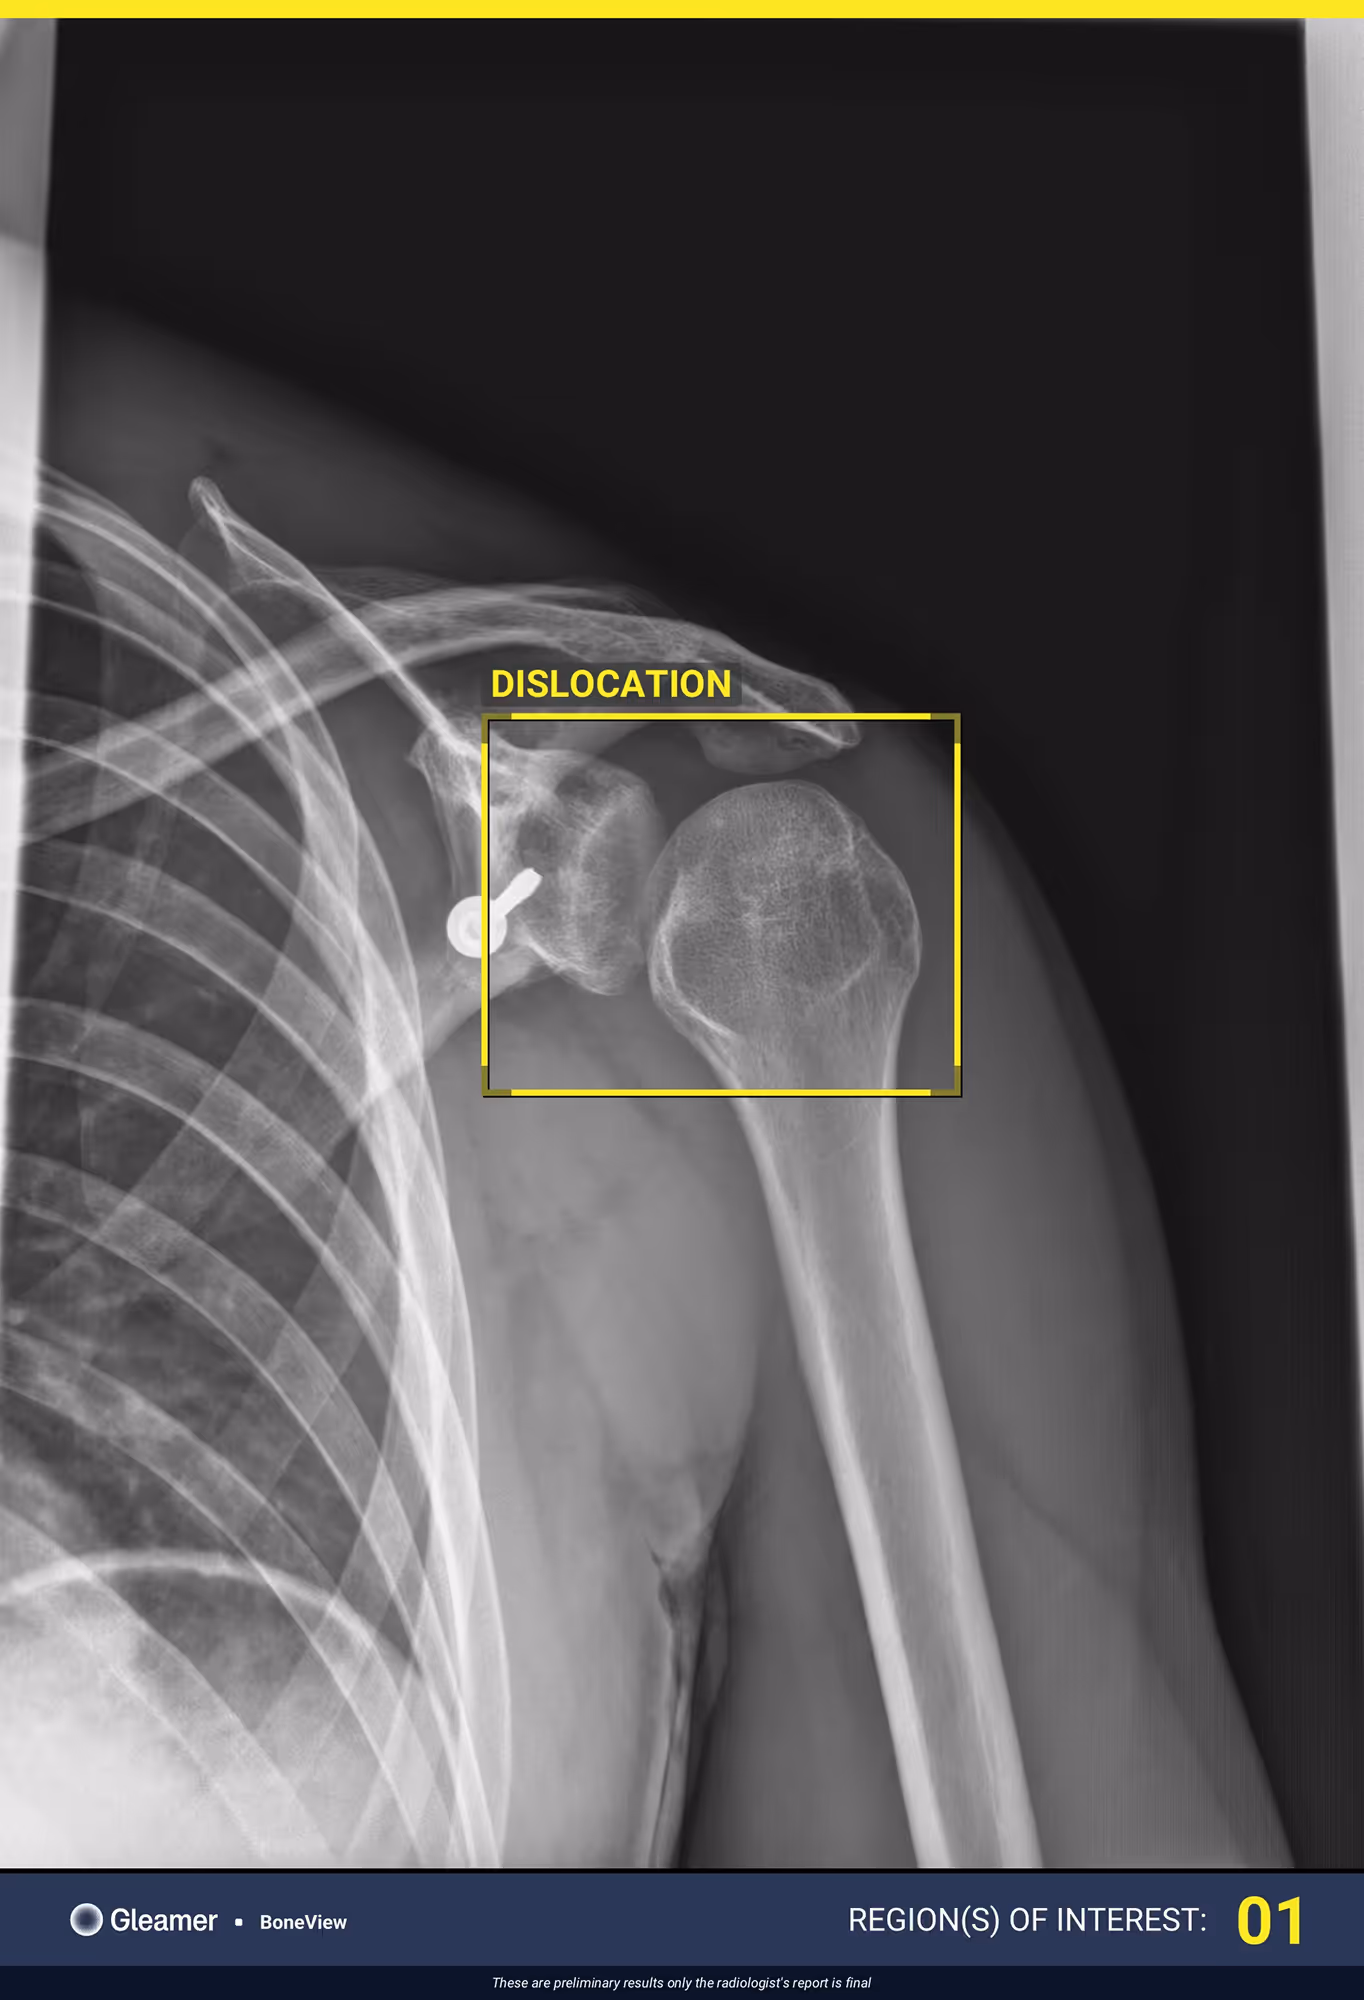

Indication

A 29-year-old male under the influence of alcohol with total functional impotence of the left arm.

Results

BoneView detected a posterior glenohumeral dislocation.